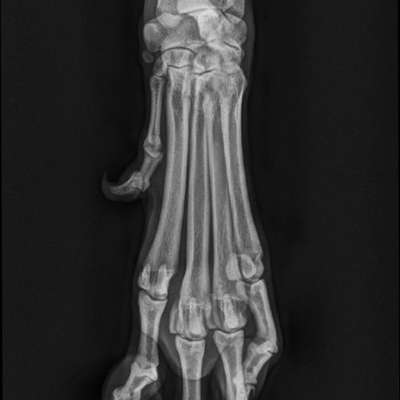

Vorab: die Qualität des Bildes hier auf dem Handy reicht nicht für eine valide Beurteilung. Röntgenbilder werden an speziellen Monitoren beurteilt und das nicht ohne Grund.

Was sehen wir?

In Grün eingekreist die beiden Sesambeine. Oben die Patella und unten die beiden Sesambeine vom M. gastrocnemi (Kniekehlmuskel). Die gehören beide da hin.

In Gelb die Wachstumsfuge des Schienbeins.

In Rot ist 1. das, was ich für die Knochenhautentzündung halten würde am Oberschenkel.

Rot 2 könnte man tatsächlich als Gelenk-Chip interpretieren, allerdings ist die Aufnahme etwas verkippt, das mag also auch an der Überlagerung liegen.

Oben wo der Kringel ist. Da ist der Knochen aufgetrieben. Ist ja eine andere Röntgenperspektive und anderes Gelenk.